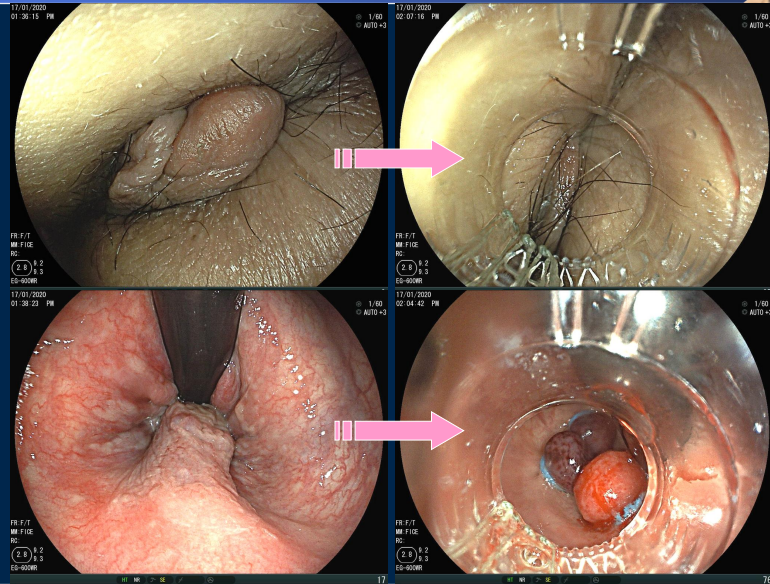

内痔的内镜下治疗—内镜下套扎术

与硬化剂注射术

痔的套扎和硬化注射治疗是一种常用的内痔治疗技术,是一种有效、快速、简单和经济的内痔治疗技术。镜下痔套扎术可以经由完整的肠道检查后,可以通过翻转肠镜镜头的姿态对肛门齿状线以上的痔疮进行吸引和套扎,将小的痔疮注射硬化剂,以减少术后疼痛。在单次的手术中,可以对多点进行同时套扎和注射,避免多次手术治疗。可以在无麻醉下实施,短时间即可完成治疗,为广大痔疮患者的微创治疗提供了新的选择。